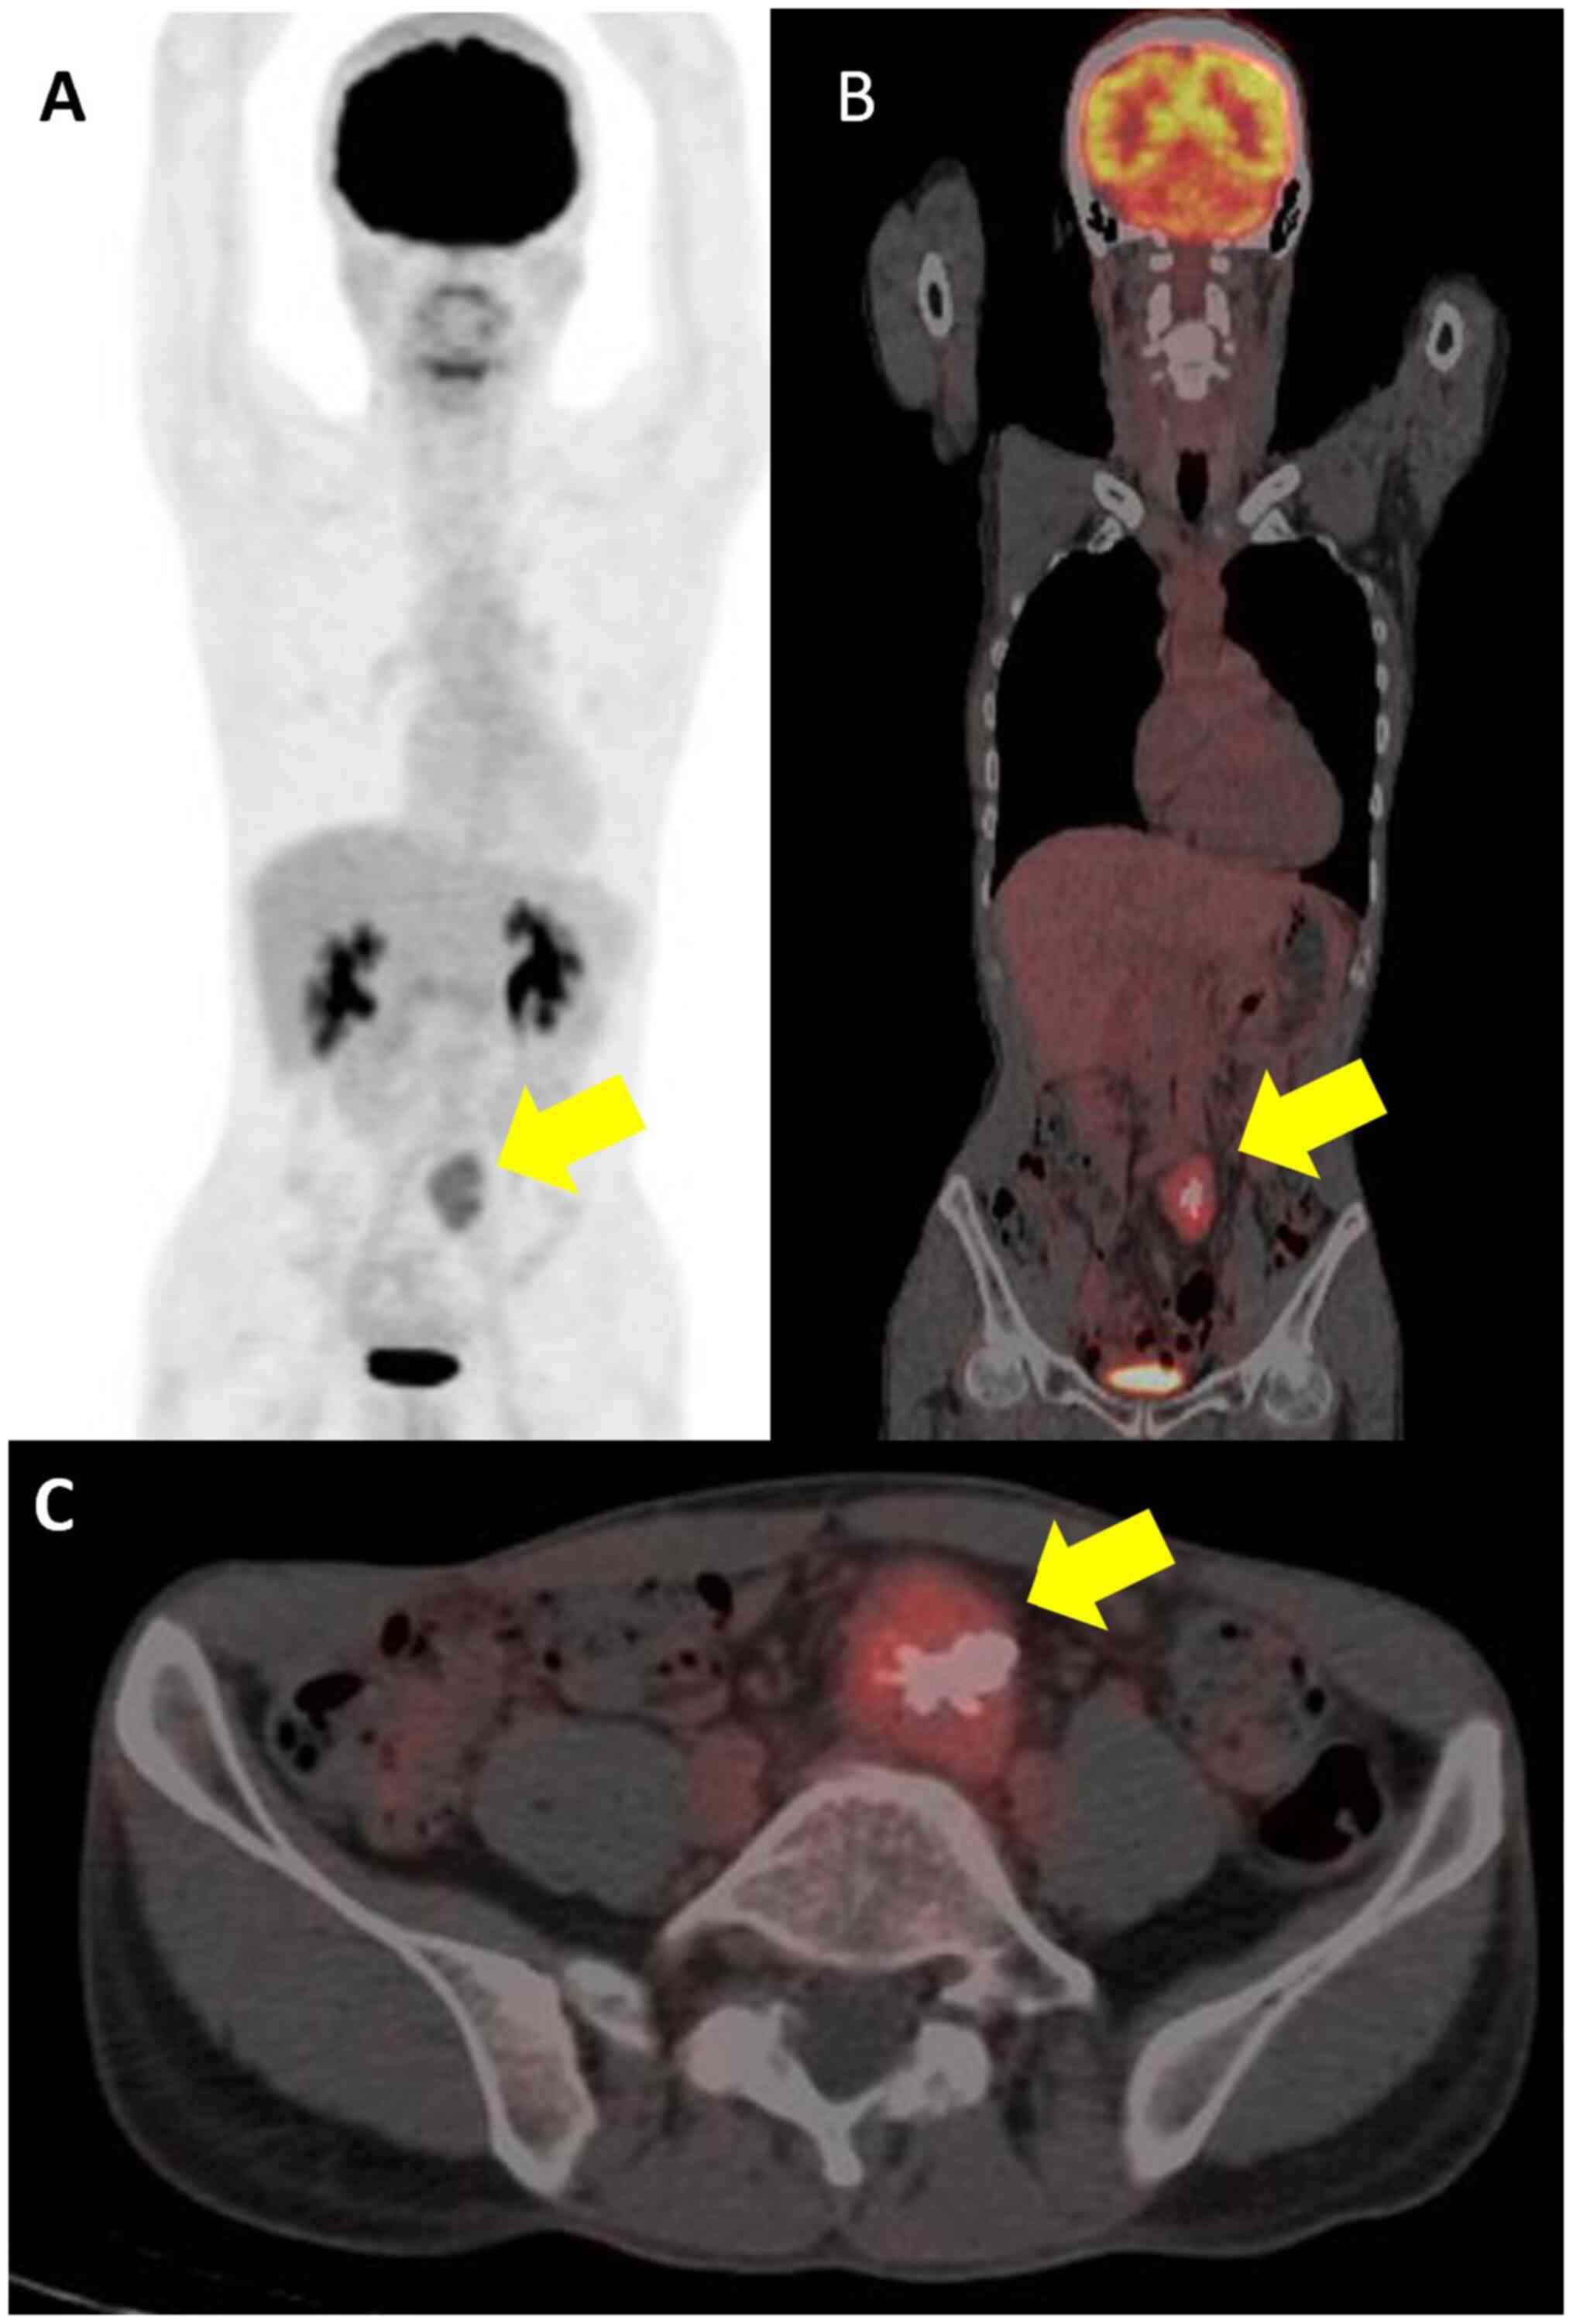

A 44-year-old man presented with a history of diarrhea at another hospital. He was diagnosed with acute enteritis with computed tomography (CT), and the diarrhea was relieved after a few days. The CT scan incidentally revealed a pelvic retroperitoneal mass with calcification, and he was referred to Osaka University Hospital. The patient underwent appendectomy for appendicitis 30 years ago, and had no viral infection or history of any other diseases. The pelvic calcification was previously identified in previous abdominal X-rays, but further examination was not performed. Physical examination revealed no abnormal symptoms. Laboratory blood tests, including for tumor makers (CA19-9 and carcinoembryonic antigen) were normal. Any abnormal finding was not detected by colonoscopy. The abdominal contrast-enhanced CT scan revealed a well-defined 50x30 mm mass behind the sigmoid mesenteric, under the bifurcation of the aorta in the pelvic retroperitoneal. Non-enhanced phase imaging revealed coarse calcification inside the mass, and evident contrast enhancement was observed in the mass during the arterial phase (Fig. 1). Magnetic resonance imaging (MRI) also revealed a well-defined 50x30 mm solid mass situated in the pelvic retroperitoneal. The mass demonstrated heterogeneous and moderately hyperintense signal intensity, and the low signal intensity corresponded to calcification in the T2-weighed images and diffusion-weighted images (Fig. 2). A positive emission tomography/CT scan was performed to exclude the possibility of paraneoplastic manifestations of a primary tumor, and it revealed a 50x30 mm space-occupying lesion with hypermetabolic activity (SUVmax at 4.1) (Fig. 3). Possible differential diagnosis based on the images were CD, primary mesenteric gastrointestinal stromal tumor or leiomyoma. At first, a diagnosis of CD was doubted as the tumor had calcification, exhibited a strong contrast in imaging, had an uniform edge and a relatively uniform inside on the abdominal CT scan; the tumor was generally isointense on T1 weighted images and hyperintense on T2 images (8). Surgical resection following embolization was suggested. Angiographically, the tumor was hypervascular with a dense capillary blush, and it was supplied by the middle sacral artery (Fig. 4). The vasculature of the mass was embolized by DMSO and the patient was operated on the following day.

PET CT scan findings. (A and B) PET CT scan sagittal. (C) PET CT scan axial; the arrow shows the 50x30 mm space-occupying lesion with hypermetabolic activity (SUVmax at 4.1) in the pelvic retroperitoneal. PET CT, positron emission tomography computed tomography.